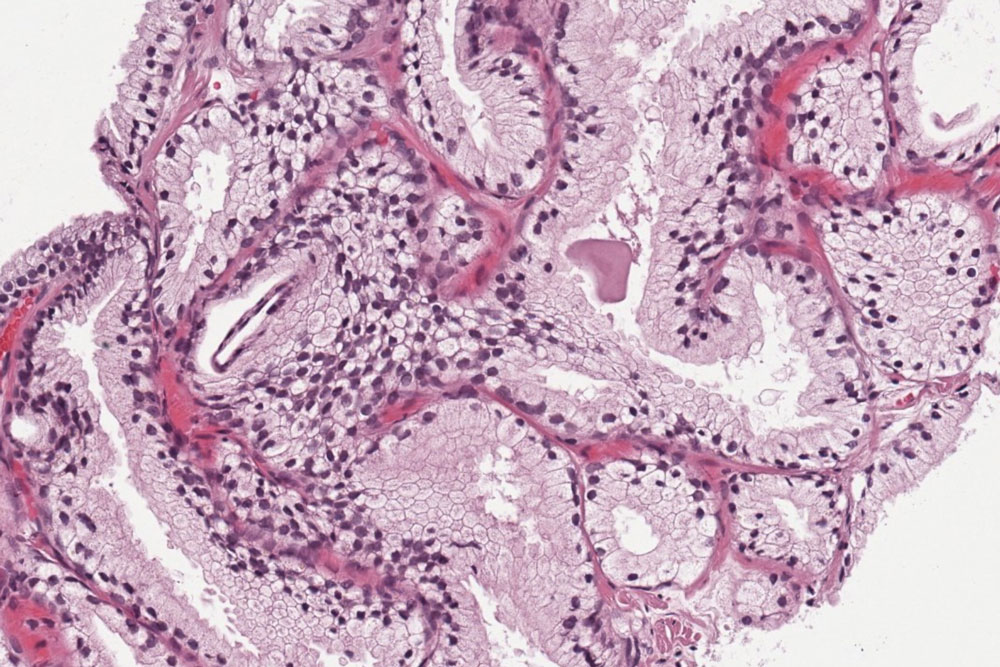

Hodenbiopsien für Tumor- und Fertilitätsdiagnostik